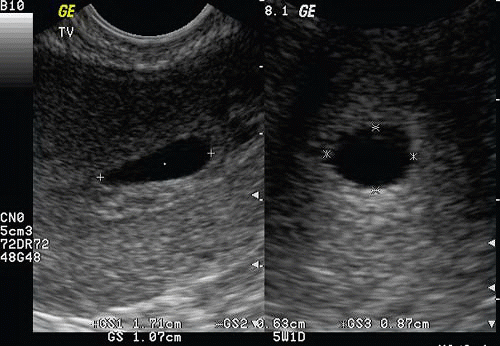

Gestational Age By Crl Calculator. Gestation by crl is calculated: Please confirm that you would like to log out of medscape.

This Is The Reference Measurement For Estimating Gestational Age.

When the crl is 57mm in the calculator, age should be doubled as 14g and age should be 12 weeks. Gestation by crl is calculated: Gestation by lmp is calculated from the first day of the last menstrual period.